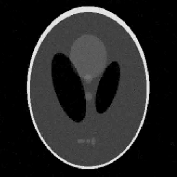

We use the Shepp-Logan phantom, available, for instance, in the Matlab Image Processing toolbox (see Figure 1). The phantom is sized , with . The projection data (i.e., sinogram) of the simulated phantom is corrupted by a white Gaussian process with zero mean and variance.

The reconstructions of the Shepp-Logan phantom are shown in Figure 4. Plots of the sparsity levels, as the iteration progresses, are reported in Figure 6. For the 120 projections case, the proposed approach converges in 885 iterations, while, in the 30 projections case, it converges in 301 iterations. As figure of merit, we use the relative error: the obtained values are summarized in Table 2, where we also report the values of the relative error obtained for the FBP reconstructions.